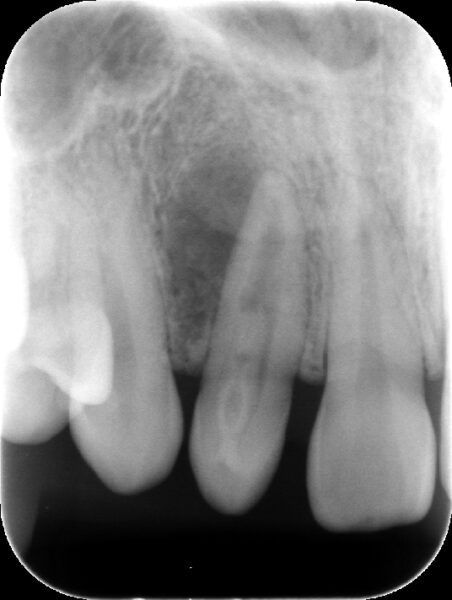

【術前レントゲン】

側方に骨欠損が認められます。(根の先の黒い部分)

歯内歯という珍しい形態を示しています。